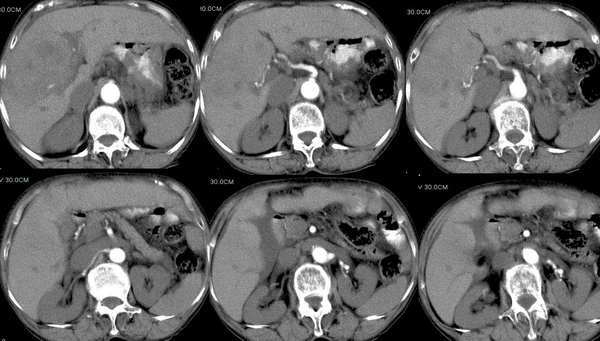

门脉期

可以肯定为肝癌;首先要指出的是,这个病例的三期扫描不规范,动脉期时间太早了,而门脉期的表现却是动脉期的表现,肾脏皮髓质交界清晰,说明处在动脉期但又略晚了点,看肝癌表现,以动脉晚期最为可靠,即动脉显影明显,脾脏呈花斑样强化,门脉初步显影,此表现为诊断肝癌最可靠的时期。这个病例肝脏有硬化表现,合并腹水,增强后病灶明显强化且边界不清,肝动脉异常增粗,门脉右支受侵,右后叶也有一处小病灶,为子灶。我的诊断为:肝右叶原发浸润型肝癌,肝硬化,门脉高压,腹水。下肢浮肿,可能为下腔静脉癌栓形成。

肝硬化、肝癌合并肝内转移、门静脉右支、及下腔静脉可以看到充盈缺损!看来,门静脉右支及腔静脉都有瘤栓形成了![emb2]